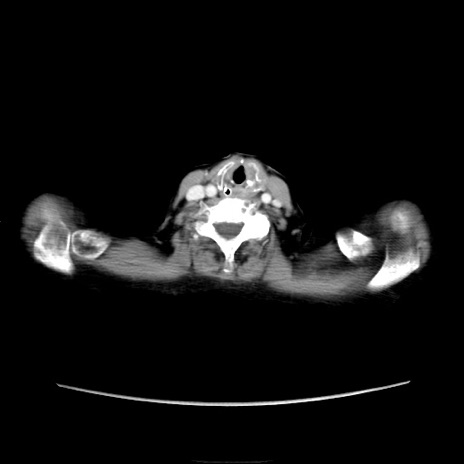

冠状断像

他院CT